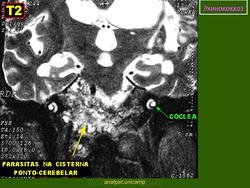

Патоморфология. Эхинококк — пузырь с довольно толстой слоистой хитиновой оболочкой, наполненный прозрачной жидкостью, содержащей янтарную кислоту. Различают эхинококк однокамерный и многокамерный, или альвеолярный. Эхи'нококк вызывает в мозге реактивное воспаление, что приводит к образованию плотной капсулы, наружные слои которой инфильтрированы лимфоидными, плазматическими и эозинофильными клетками. Располагается он чаще всего в глубине полушарий. Величина эхинококка колеблется от горошины до куриного яйца. В некоторых случаях он растет кнаружи и, выходя на поверхность мозга, может узурировать кость.

Клиника эхинококка напоминает клинику опухоли головного мозга. При нем бывает выражен гипертензионный синдром, сочетающийся с очаговыми симптомами. Характерные изменения развиваются в костях черепа: они истончаются над эхинококком и в отдельных случаях могут разрушаться, открывая опухоли выход наружу. Эхинококковый пузырь в этих случаях прощупывается на поверхности черепа в виде плотной флюктуирующей опухоли. В крови эозинофилия. В ликворе бывают положительные белковые реакции, небольшой эозинофильный плеоцитоз, янтарная кислота.

Диагноз. Эхинококк головного мозга обычно диагностируется как опухоль. Мысль об эхинококке возникает при наличии у больного эхинококка печени или других органов. Имеют значение также эпидемиологические данные при контакте с животными. Диагностическое значение имеет эозинофилия в крови и спинномозговой жидкости. Для диагностики эхинококка пользуются реакциями Каццони и Гедина—Вейнберга. Реакция Каццони заключается во внутрикожном введении больному жидкости эхинококкового пузыря. Реакция считается положительной, если через 5—10 мин после инъекции появляется местный воспалительный инфильтрат. Реакция Гедина—Вейнберга состоит в связывании комплемента при смешении крови больного с антигеном (жидкостью эхинококкового пузыря).